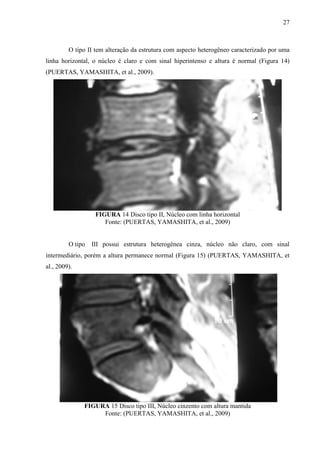

O tipo II tem alteração da estrutura com aspecto heterogêneo caracterizado por uma

linha horizontal, o núcleo é claro e com sinal hiperintenso e altura é normal (Figura 14)

(PUERTAS, YAMASHITA, et al., 2009).

FIGURA 14 Disco tipo II, Núcleo com linha horizontal

Fonte: (PUERTAS, YAMASHITA, et al., 2009)

O tipo

III possui estrutura heterogênea cinza, núcleo não claro, com sinal

intermediário, porém a altura permanece normal (Figura 15) (PUERTAS, YAMASHITA, et

al., 2009).

FIGURA 15 Disco tipo III, Núcleo cinzento com altura mantida